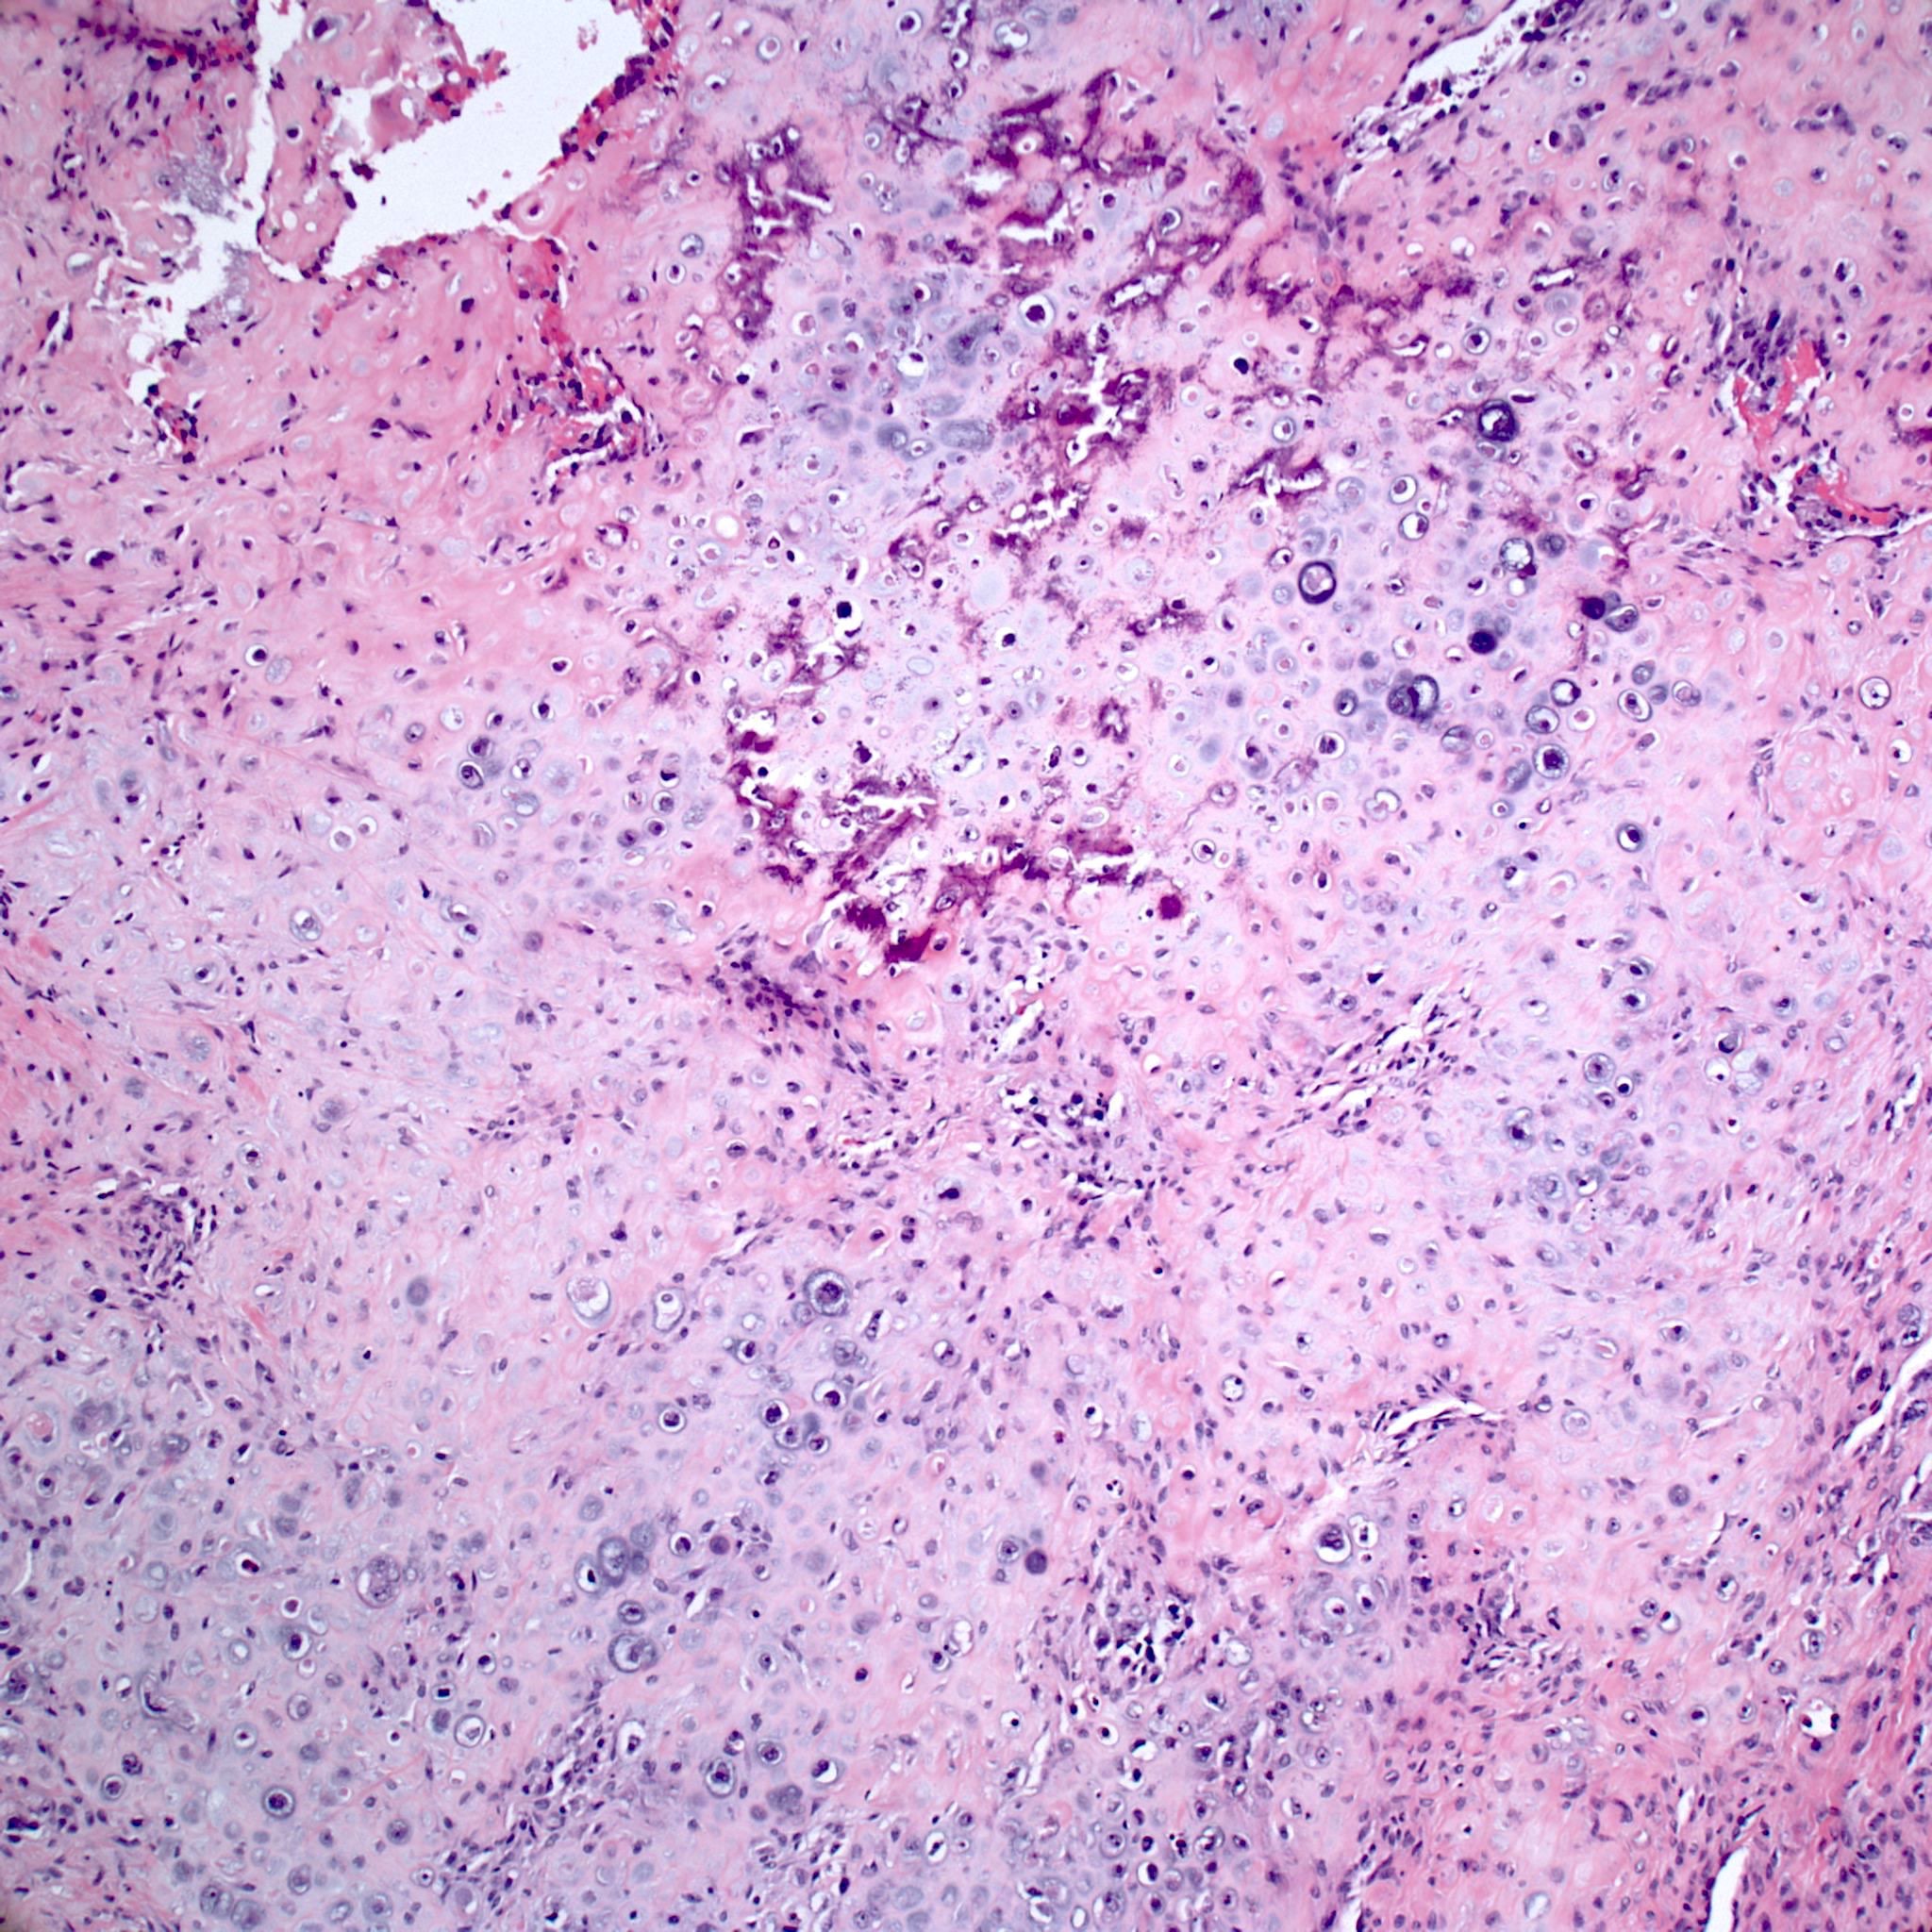

- Conventional (high grade intramedullary) osteosarcoma (Eur J Cancer 2002;38:1218, Am J Clin Pathol 2006;125:555):

- Permeative growth: intramedullary permeative growth (replacement of medullary space, surrounds and erodes native trabeculae, fills Haversian systems) and cortical destruction with soft tissue invasion

- Neoplastic cells: marked atypia (pleomorphic, hyperchromatic)

- Multiple cell morphologies often present in 1 tumor (epithelioid, plasmacytoid, spindled, small round cells, clear cells, giant tumor cells)

- Mitotic figures are easily demonstrable and atypical mitotic figures may also be identified

- Neoplastic bone (necessary for diagnosis): no minimum quantity necessary

- Most common: filigree / lace-like disorganized woven bone (intimately associated with neoplastic cells)

- Broad sheets of bone

- Normalization: decreased cytologic atypia of neoplastic cells entrapped in the bone matrix

- Scaffolding (appositional neoplastic osteoid deposition): deposition of neoplastic osteoid on native trabeculae

- Nonneoplastic giant cells: ~25% of cases

- Histologic subtypes of conventional osteosarcoma: no prognostic significance

- Osteoblastic, chondroblastic and fibroblastic are based on the prominent matrix they secrete (often admixed in 1 tumor)

- Osteoblastic osteosarcoma: the predominant matrix is neoplastic bone (as described above)

- Chondroblastic osteosarcoma: the predominant matrix is high grade cartilage (never has low grade cartilage)

- Fibroblastic osteosarcoma: spindled to epithelioid cells, often with severe atypia, which may secrete extracellular collagen (may be extensive)

- Telangiectatic osteosarcoma: the tumor is multiloculated with large blood filled spaces; high grade malignant cells and neoplastic bone in septa (the imaging differential diagnosis is with aneurysmal bone cyst)

- Other morphologic variants: giant cell rich variant (numerous osteoclast-like giant cells), epithelioid variant, osteoblastoma-like variant, chondroblastoma-like variant, chondromyxoid fibroma-like osteosarcoma, clear cell variant, small cell variant

Microscopic (histologic) images

Contributed by Jesse Hart, D.O., Borislav A. Alexiev, M.D. and AFIP

A 16 year old boy had a biopsy from a 16 cm mass in the proximal humerus (see image). Which of the following is true?

C. Treatment will include neoadjuvant chemotherapy followed by resection. This is a conventional high grade osteosarcoma.